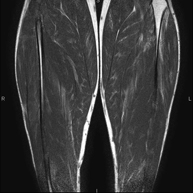

- Thigh MRI

Ideal examination for studying injuries to the hamstrings and quadriceps, which are frequently injured in athletes. It also allows for a good assessment of tendons and peripheral nerves. It lasts approximately 20 minutes. It is a radiation-free procedure.

- Leg MRI

Examination to study injuries to tendons, muscles and peripheral nerves. Very useful for diagnosing fibrillar tears in twins. It lasts approximately 18 minutes. It is a radiation-free procedure.